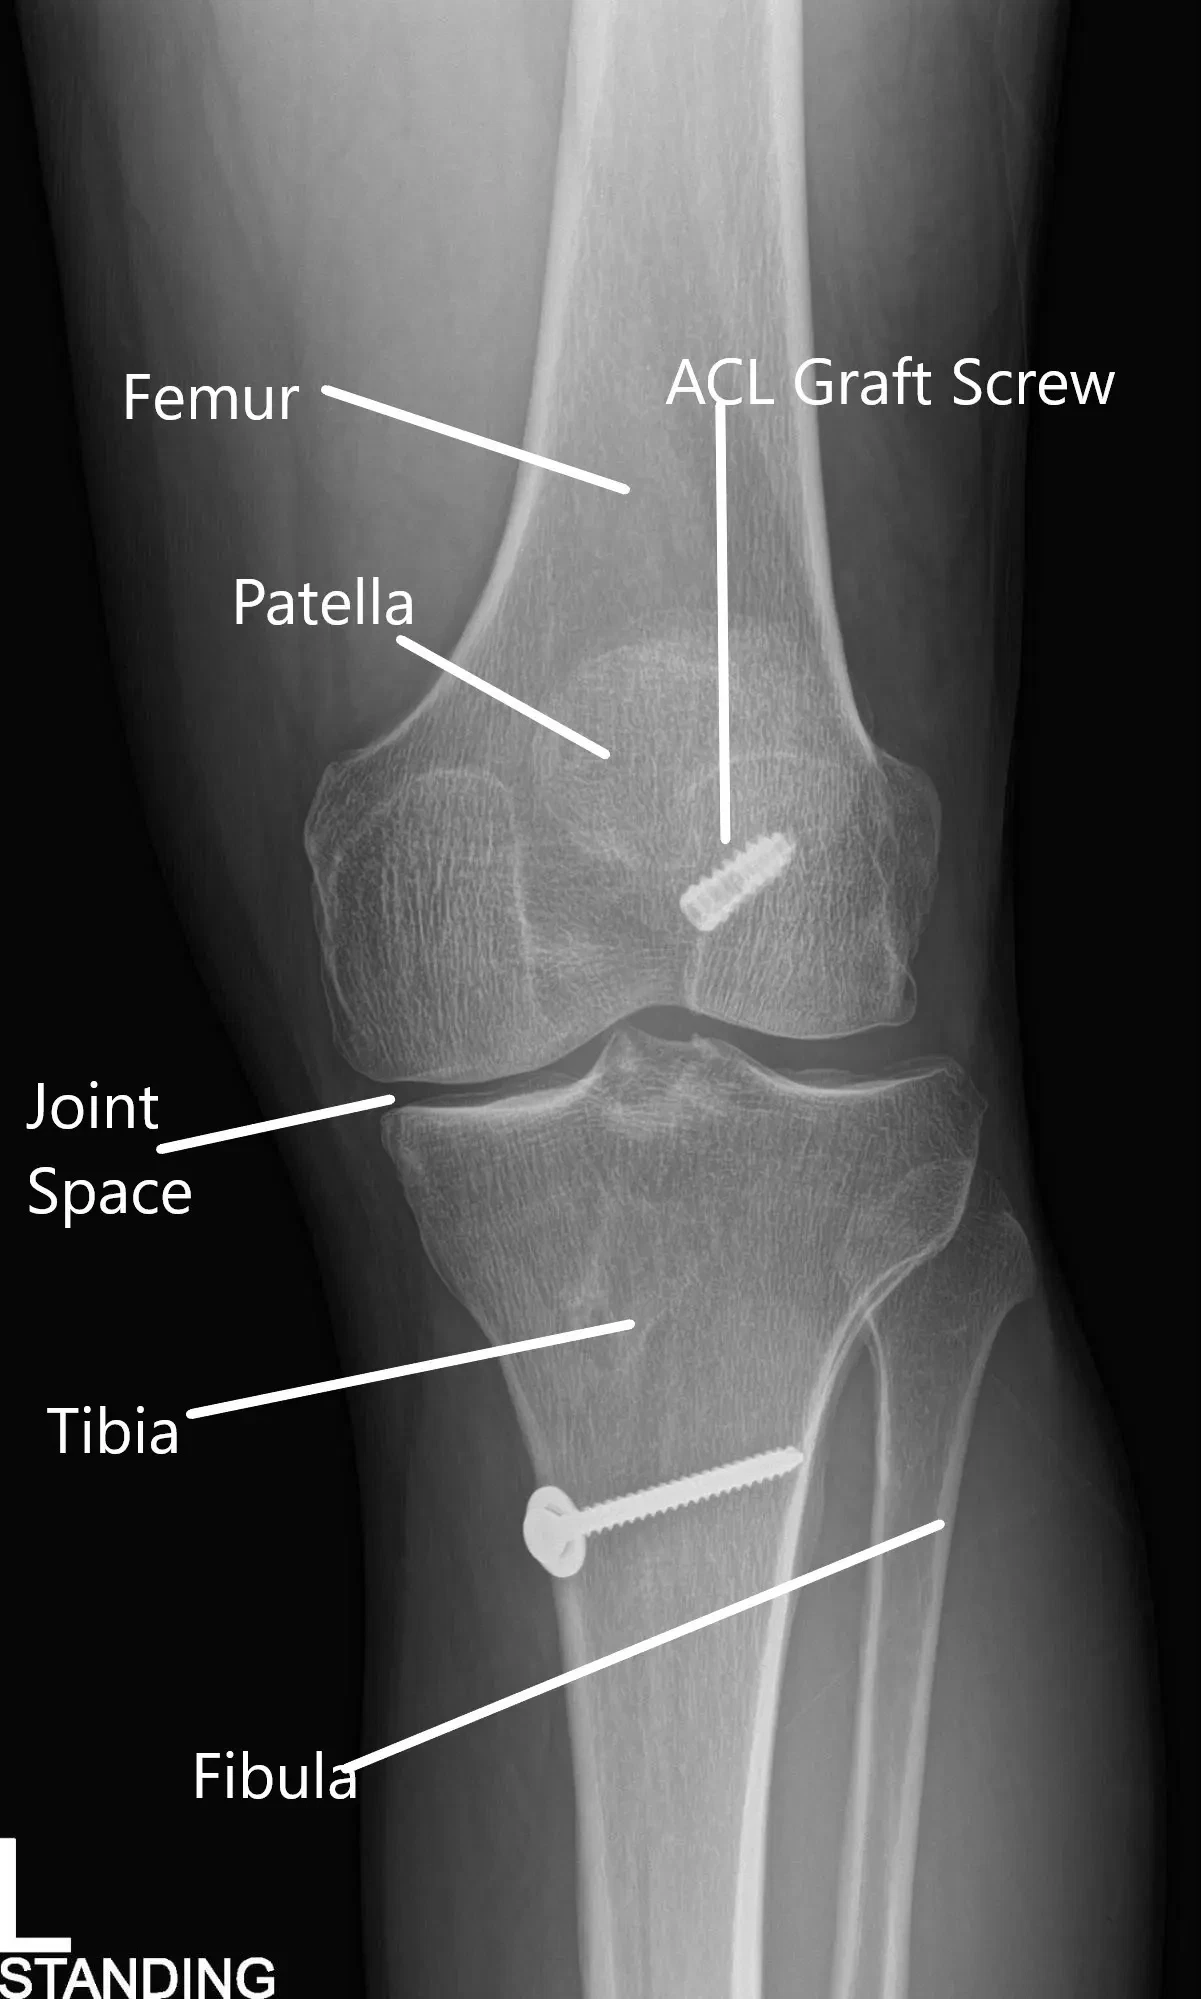

X-ray of the left knee in AP and Lateral views.

An X-ray of the left kee suggested a moderate narrowing of the medial joint compartment and status post ACL reconstruction.